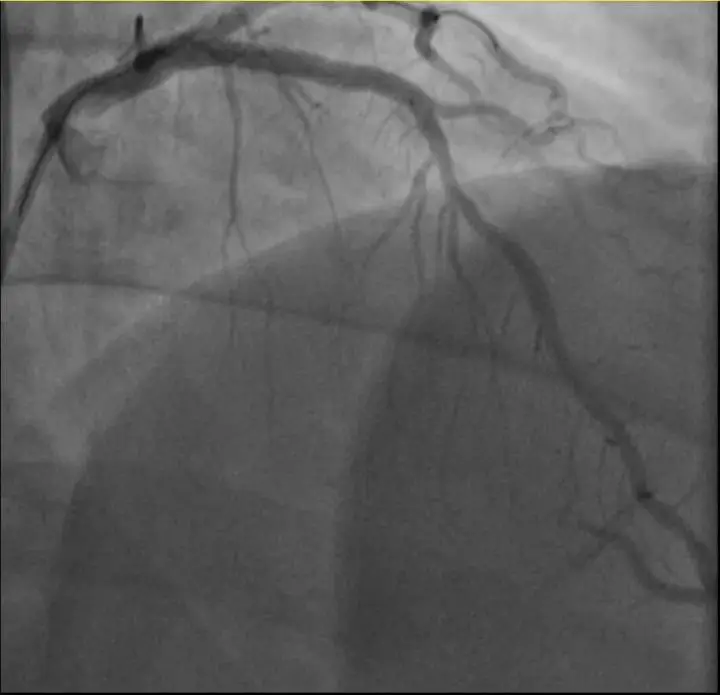

孙先生(化名)身高173cm,体重约90公斤,是一位羽毛球教练。一年前,他因胸闷就诊时被查出心脏右冠中段、远端钙化斑块,以及心脏三支主要血管之一前降支中段60%狭窄。当时考虑到没有三高的危险因素(可能为早发冠心病家族史),孙先生也坚信自己可以通过运动恢复健康,因此拒绝了介入治疗,只接受药物治疗。

介入治疗前影像图。